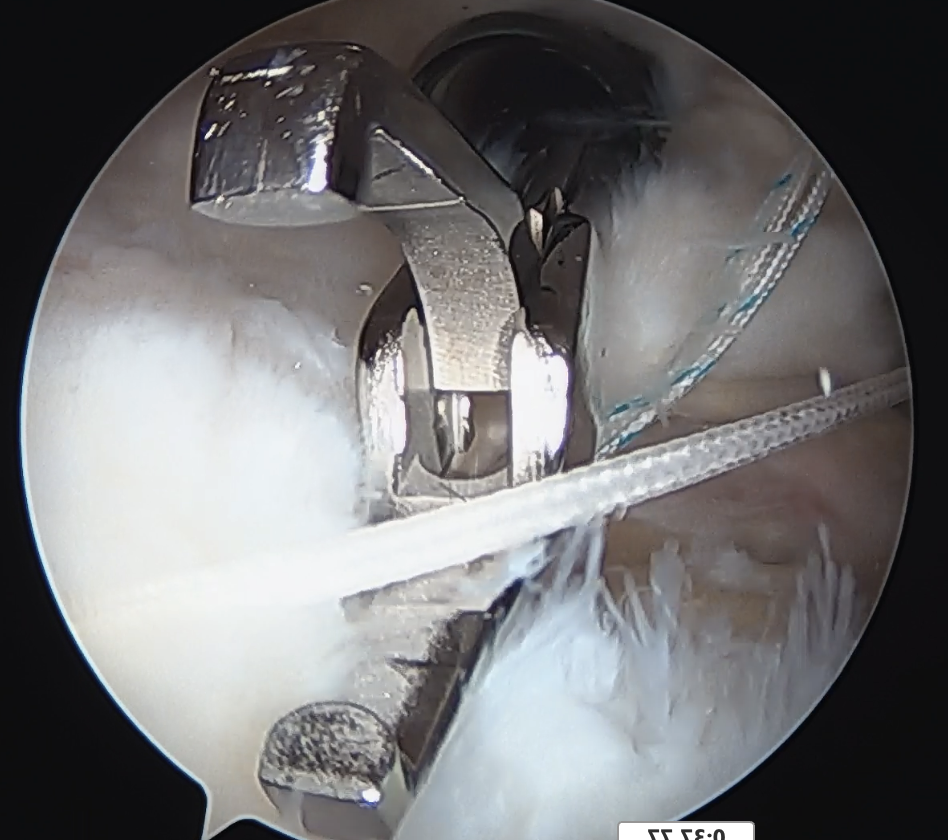

Pass sutures through medial cuff tendon

- camera posterior

- suture passer via lateral portal

- retrieve sutures through anterior portal

- repeat

- tie medial row